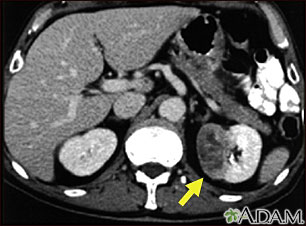

Esta TC del abdomen muestra un tumor en el riñón izquierdo, llamado hipernefroma o carcinoma de células renales, ubicado en el lado inferior derecho de la imagen.